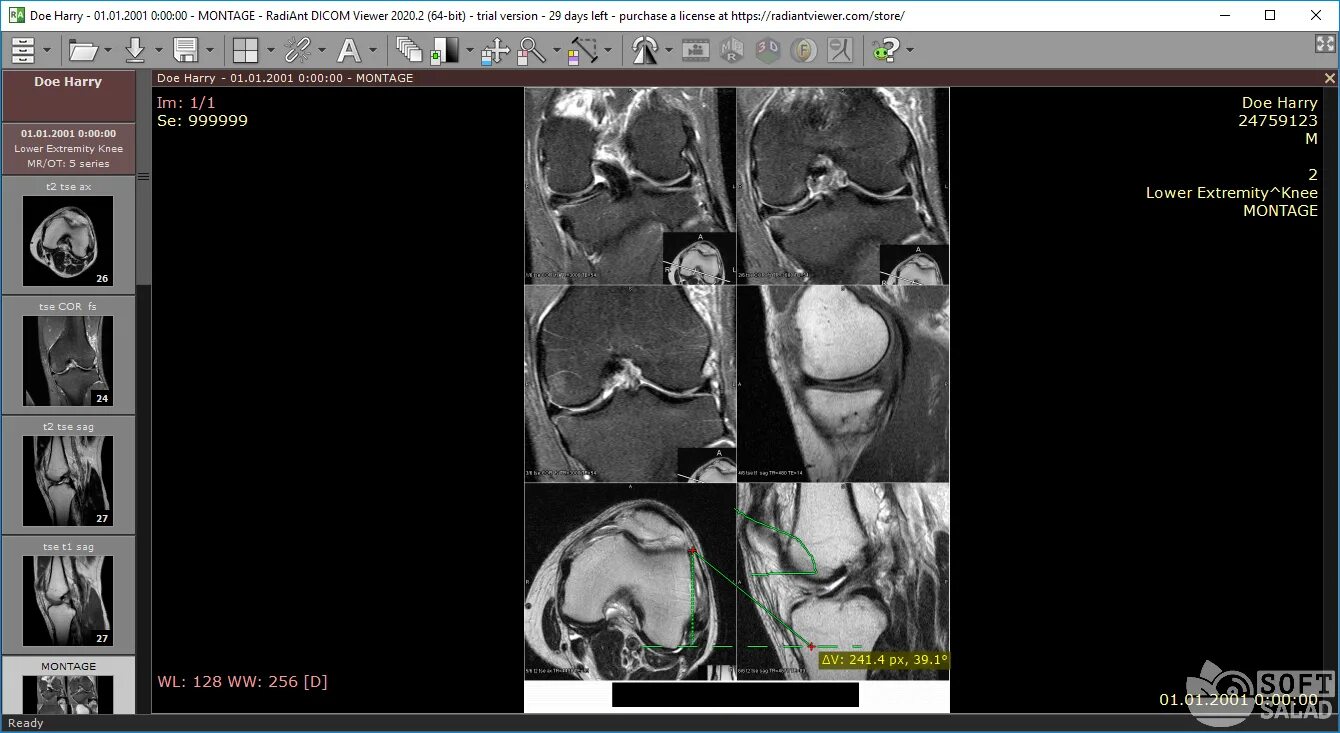

Dicomdir чем открыть снимки мрт